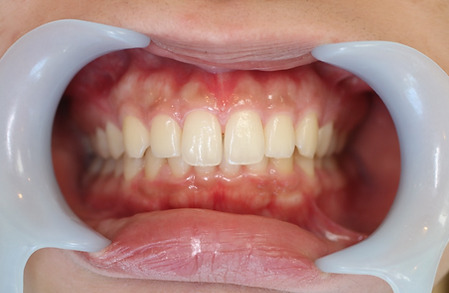

2ホワイトニング【治療例1】

治療前

治療後